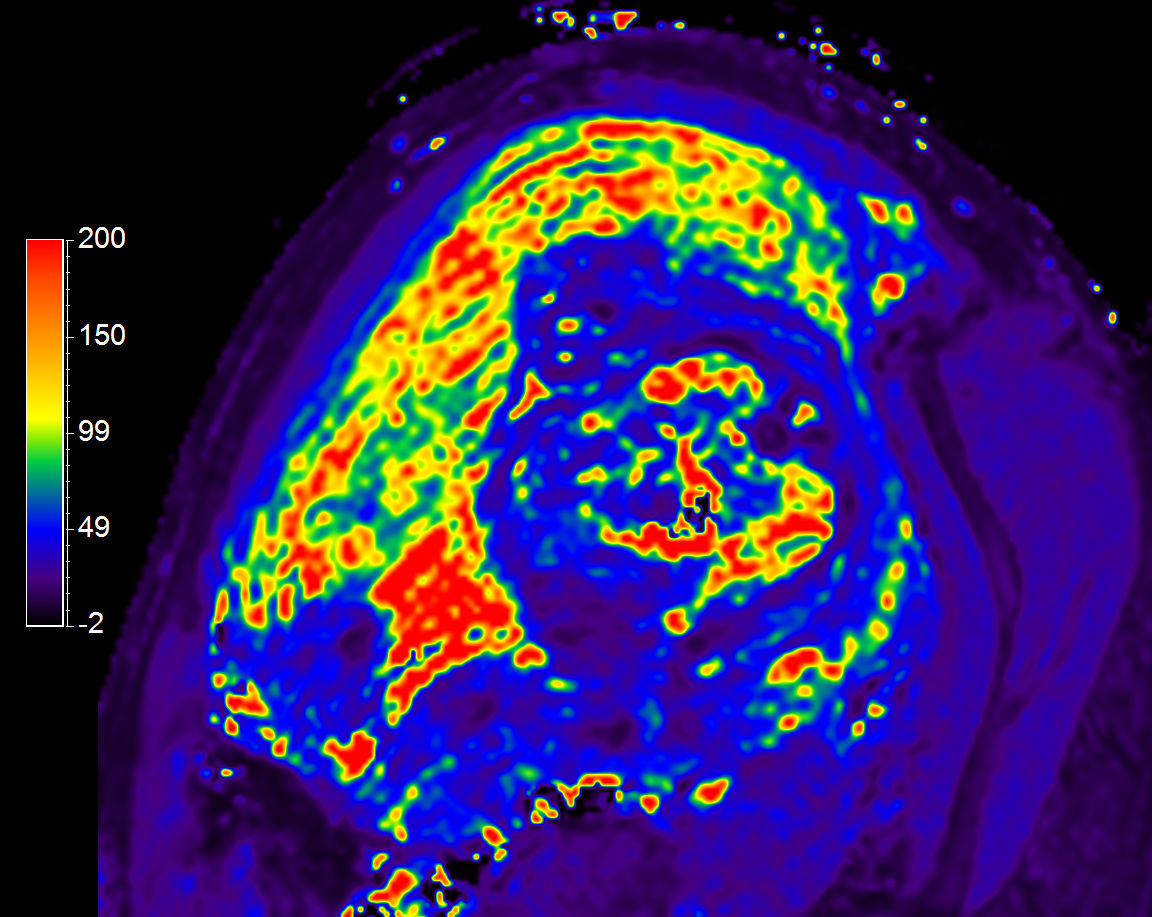

T1 Map

T2 Map

T2* Map